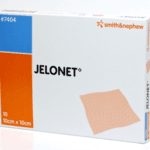

Apply jelonet